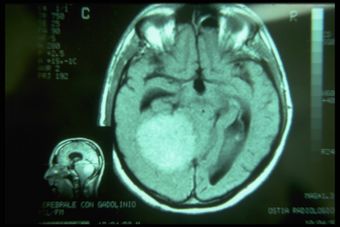

MRI of the brain, using Turbo Spin Echo, Fluid Attenuated Inversion Recovery, and Gradient Echo sequences, was conducted before and after intravenous administration of contrast medium. Results showed the presence of a roundish area of approximately 1.5 cm in diameter located in the vicinity of the quadrigeminal cistern at the level of the pineal gland. There was also a slight dilation of the supratentorial ventricular system, which appeared in the axis and was most evident in the proximity of the temporal horns, with a periventricular rim with a transependymal fluid absorption phenomenon.[1] The signal characteristics of the formation suggested a provisional diagnosis of pineal cavernoma. (Figures 2 and 3)

«Definitive diagnosis: Pineal cavernoma»